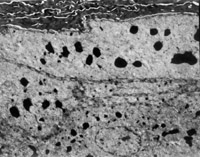

¾­MEBT/MEBOÒ½ÖÎ20Ì죬µç¾µ¹Û²ìµ½»ùÐéʵ°û²ãÓëÏËάĸϸ°ûÖ®¼äµÄ°ëÇÅÁ£ÏνÓ£¬Í¬Ê±¿É¼ûÏËάĸϸ°ûÄÚ´ÖÃæÄÚÖÊÍø½á¹¹ºÍÏßÁ£ÌåÔöÉúÑÄÔ¾£¨Í¼5-3-19¡«5-3-21£©¡£ MEBT/MEBOÒ½ÖÎ30Ììºó£¬ÉÏÆ¤×éÖ¯ÔÙÉú½¨¸´£¬ÒѸù»ùʵÏÖ£¬´´Ãæ×éÖ¯ÇÐÆ¬ÏÔʾ½ºÔ­ÏËά³ÉÊ죬·ÖÁÐÕûÆë£¨Í¼5-3-22£©£¬Ö±¾¶Îª0.1¡«0.5µm£¬²¢¿É¼ûÃ÷°µÏà¼äÖÜÆÚÐÔºáÎÆ£¨64nm£©£¬Î´¼ûµ½½ºÔ­ÏËάŤÇúºÍ³ÊÐýÎÓ×¢²Ë»¨µÈ²¡Àí״̬¡£

5-3-22 MEBT/MEBOÒ½ÖÎ30Ì죬ÕûÆë·ÖÁеĽºÔ­ÏËά£¬ÏËά¾ùÔÈÒ»ÖÂÖ± ¾¶ 0.1¡«0.5µm£¬ÓÐÃ÷°µÏà¼äµÄÖÜÆÚÐÔºáÎÆ£¨64nm)